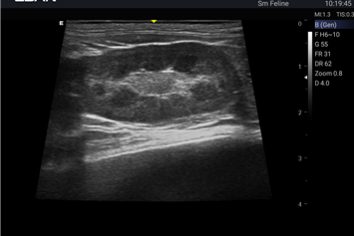

Revolutionary platform results in superb detail resolution, particularly at depth.

Tissue Adaptive Imaging (TAI) continuously and automatically optimizes imaging